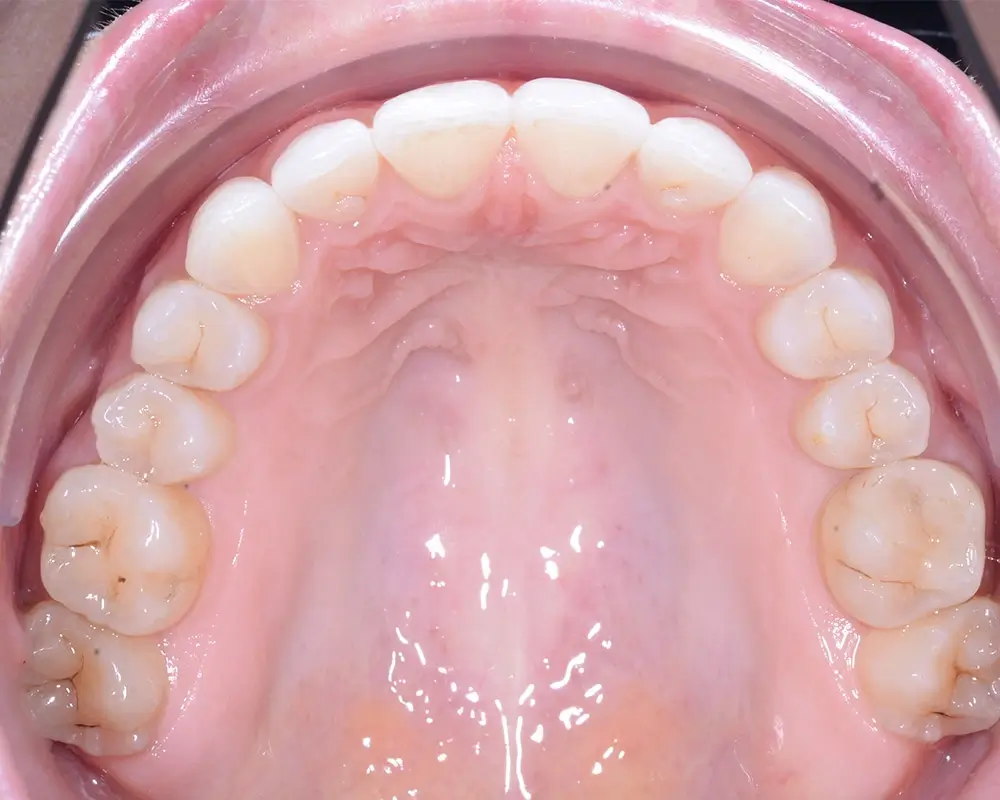

Дистальный прикус - Кейс 4

Эффективность устранения дефекта прикуса посредством элайнеров FlexiLigner.

Результаты лечения